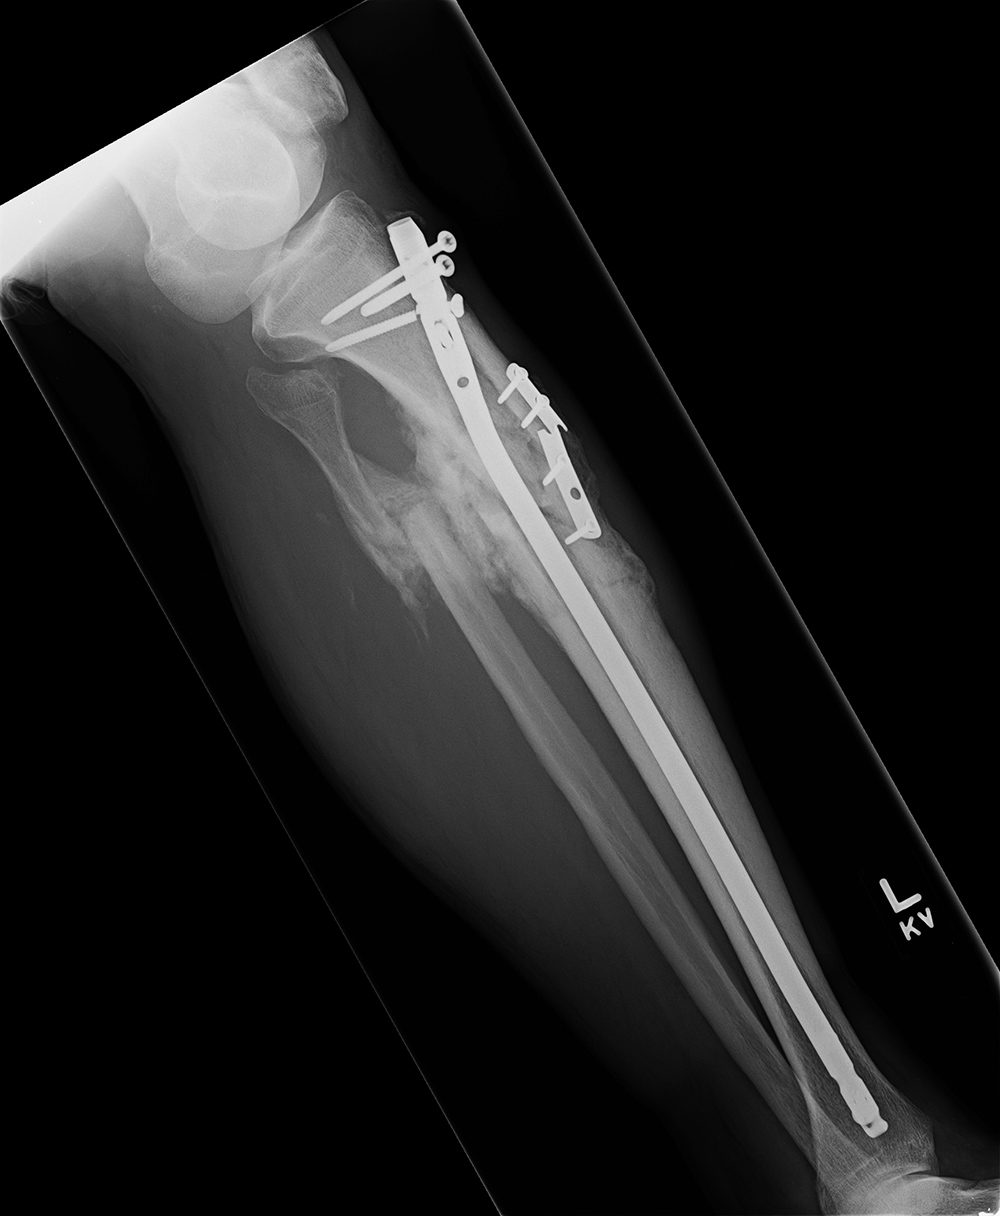

| Failure of fracture fixation due to ambulating against advice |

| Male patient with proximal tibia and fibula fractures treated by intramedullary nail and supplemental one-third tubular plate. Initial intraoperative fluoroscopic AP and lateral images (left two images) show the plate (arrow on lateral image). The patient ambulated against advice and was lost to follow-up. Two months later he again presented (right two images) to the clinic. There is now tibia fracture migration, and the proximal medial to lateral interlocking screw has backed out (AP view). The lateral view demonstrates fracture displacement with flexion deformity. The nail has troughed outside the proximal anterior tibia and is sitting within the soft tissues. The supplementary plate is broken, there is a broken interlocking screw, and abundant fracture callus is present. |